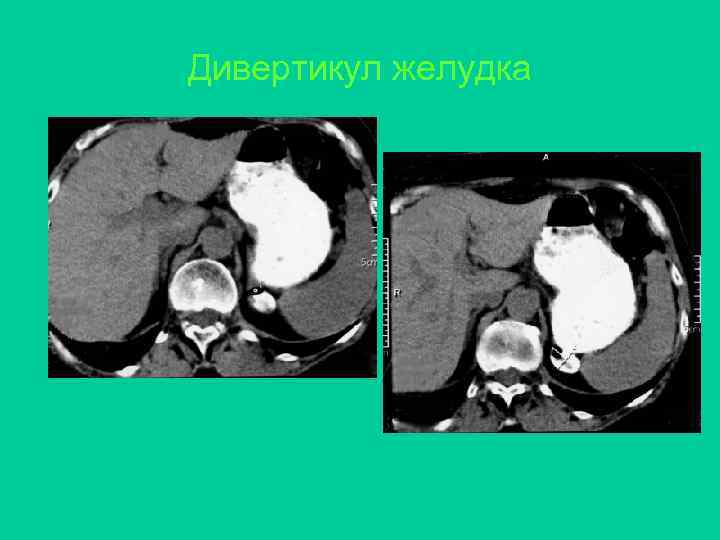

Дивертикул желудка